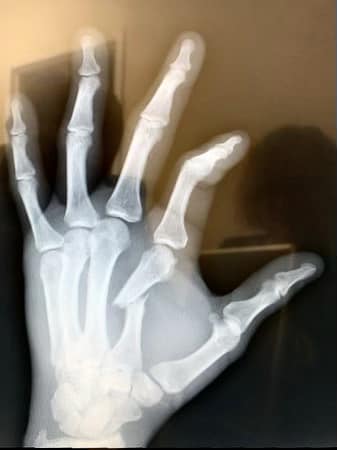

️A HARAG NEM JÓ TANÁCSADÓ

Egy munkahelyi értekezlet után szerette volna levezetni mérgét az a 45 év körüli férfi, aki ököllel ütött hatalmasat a tárgyaló falába hét elején Budapesten. Az…